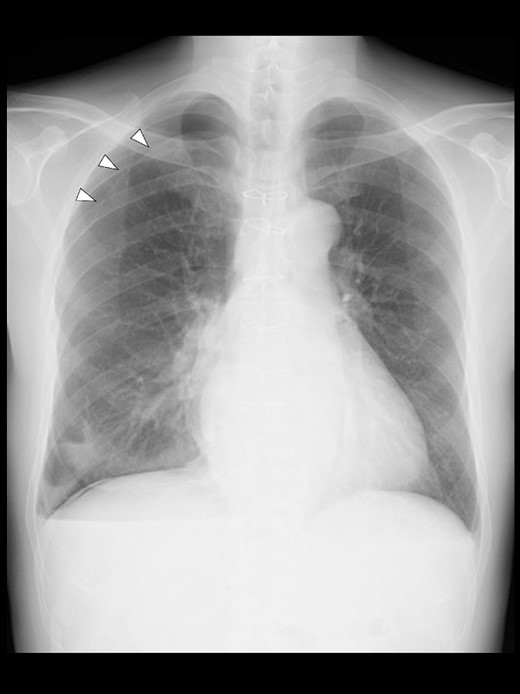

Even though the patient did not receive supplemental oxygen in the ward, SpO2 remained at 98%. Chest radiographs were not taken on the day of surgery. However, a chest radiograph taken in the upright position on postoperative Day (POD) 1 revealed a pneumothorax on the right side (Fig. 2), although he had no respiratory symptoms. Radiographs on PODs 2 and 3 revealed the pneumothorax remaining unchanged (Fig. 3). The patient was discharged from the hospital on POD 3 without any respiratory symptoms. A chest radiograph taken on POD 19 showed no remaining pneumothorax.

A chest radiograph in the upright position on POD 3 showing a residual right pneumothorax (arrowheads).